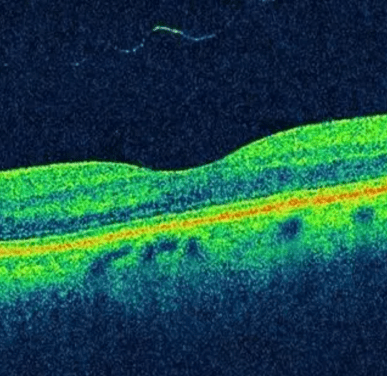

Optical Coherence Tomography (OCT) – OCT is a non-invasive imaging test that measures key areas within the retina, such as the retinal nerve fiber layer, which are important for understanding the integrity of the optic nerve. In MS, the thinning of these layers can indicate nerve damage and neurodegeneration, which are significant contributors to disability and disease progression.  According to a 2018 review, OCT’s ability to detect these changes makes it a valuable tool for diagnosing MS and monitoring its course over time. Moreover, the extent of thinning observed with OCT has been linked to the severity of brain atrophy and the level of physical and cognitive disability in MS patients, underscoring its potential in assessing the overall impact of the disease on the nervous system.

nerve fiber

Image from https://www.rsipvision.com/explaining-oct-scans/